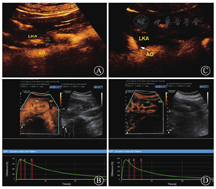

结果显示,较支架置入前,支架置入后和术后3个月随访时的皮质血流灌注明显改善,表现为上升支、下降支AUC和峰值强度均明显升高,而上升时间、达峰时间和平均渡越时间均明显延长(均为P<0.05);较支架置入后,术后3个月时的下降支AUC、上升时间和峰值强度均无明显差异(均为P>0.05),而上升支AUC明显增大,达峰时间和平均渡越时间均有明显缩短(均为P<0.05)(图1,表2)。

LKA:左肾动脉;AO:主动脉;A:支架置入前显示左肾动脉中段狭窄85%(见箭头);B:支架置入前的左肾皮质血流灌注明显减退;C:支架置入后左肾动脉中段狭窄解除(见箭头);D:支架置入后的左肾皮质血流灌注明显改善